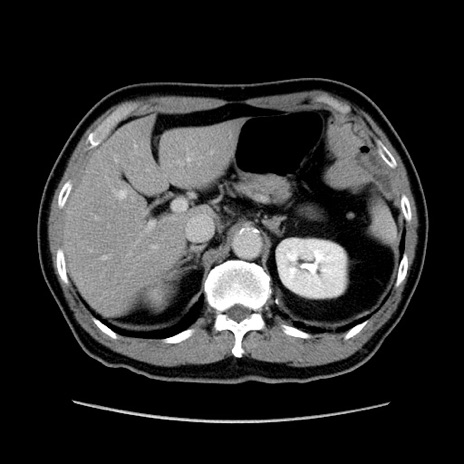

症例34(横断像)

【症例】60歳代 男性

【主訴】右鼠径部膨隆

【現病歴】1年程前より右鼠径部膨隆あり。自己にて還納可能だったため放置していた。3時間前より右鼠径部の脱出を認め、還納困難となり受診。

【既往歴】高血圧

【身体所見】右鼠径部に小児頭大の膨隆あり。弾性硬であり、用手還納は困難。左鼠径部にも膨隆を認める。脱出はなし。

【データ】WBC 15500、CRP 測定なし